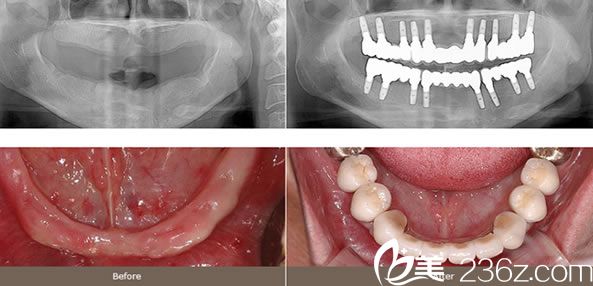

案例二:整体种植牙效果怎么样

整体植牙牙齿的大部分或者整体丧失的情况下来用植牙的方式恢复牙齿的意思。因为同时植入很多颗牙齿的施术是很高难度的,所以需要丰富施术经验和对齿槽骨或者上下颌的解刨学构造非常熟练才可以,同时还需要为了牙齿形状吻合和正确的咬合需要提前预想出牙齿的模样和位置。

整体(全颚)植牙施术是上下两排牙齿全部设立的情况,也可以6~10颗左右分散装置。但是为了均衡订做是需要充分经验和专业知识的。同时还要通过3个不同层面的CT等缜密的监测和周密的计划来进行。